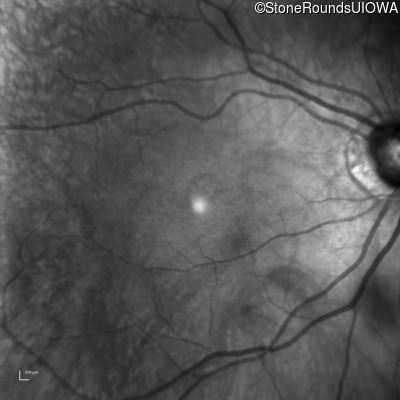

The clinical features favoring the diagnosis of RP1L1-associated occult macular dystrophy include: reduced acuity with a near-normal ophthalmoscopic appearance, a history of normal acuity in childhood; and, a "moth-eaten" appearance of the macular ellipsoid zone on OCT.

OD OS